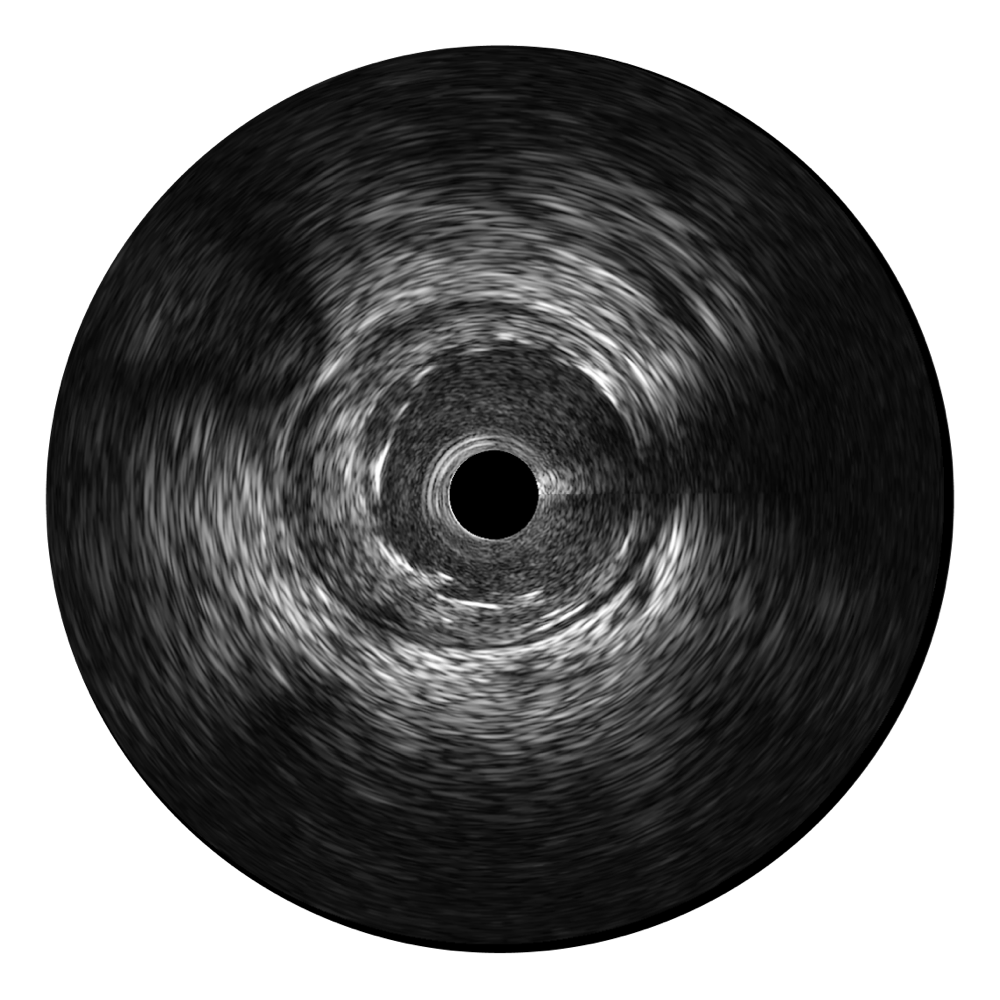

乐玩lewin国际宽频IVUS图像

对比传统IVUS导管成像,乐玩lewin国际宽频IVUS图像的近场支架梁显影更细腻,远场中膜外血管仍清晰可辨,兼顾远中近,兼顾分辨力与穿透深度